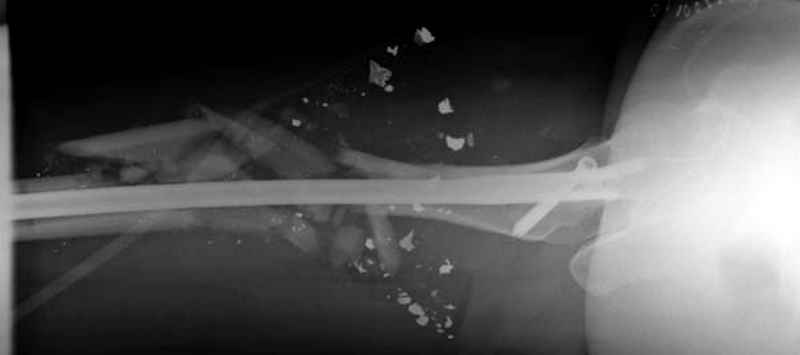

3 такие раны после удаления пули и остатков одежды можно закрыть первично

И последний